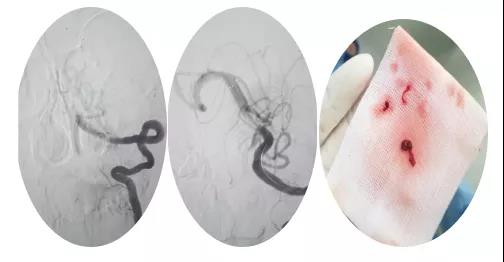

18:30手術開始,造影為基底動脈閉塞,與患者家屬充分溝通,患者家屬同意給予介入取栓治療。共取栓2次,取出少量暗紅色血栓塊。造影示:基底動脈有重度狹窄,結合患者病情演變及造影結果,考慮為動脈粥樣硬化性狹窄。根據患者造影結果,目前單純取栓無法達到預期效果,決定給予基底動脈支架植入術。根據患者基底動脈直徑選擇3.0*13mm apollo球擴支架,支架植入后造影示狹窄消失。

支架植入后患者神志轉清,四肢均可活動,左側肢體活動略差于右側,收入神經內四科病房進一步治療。術后第三天患者神志清,四肢活動基本正常,住院5天轉入當地醫院治療。?